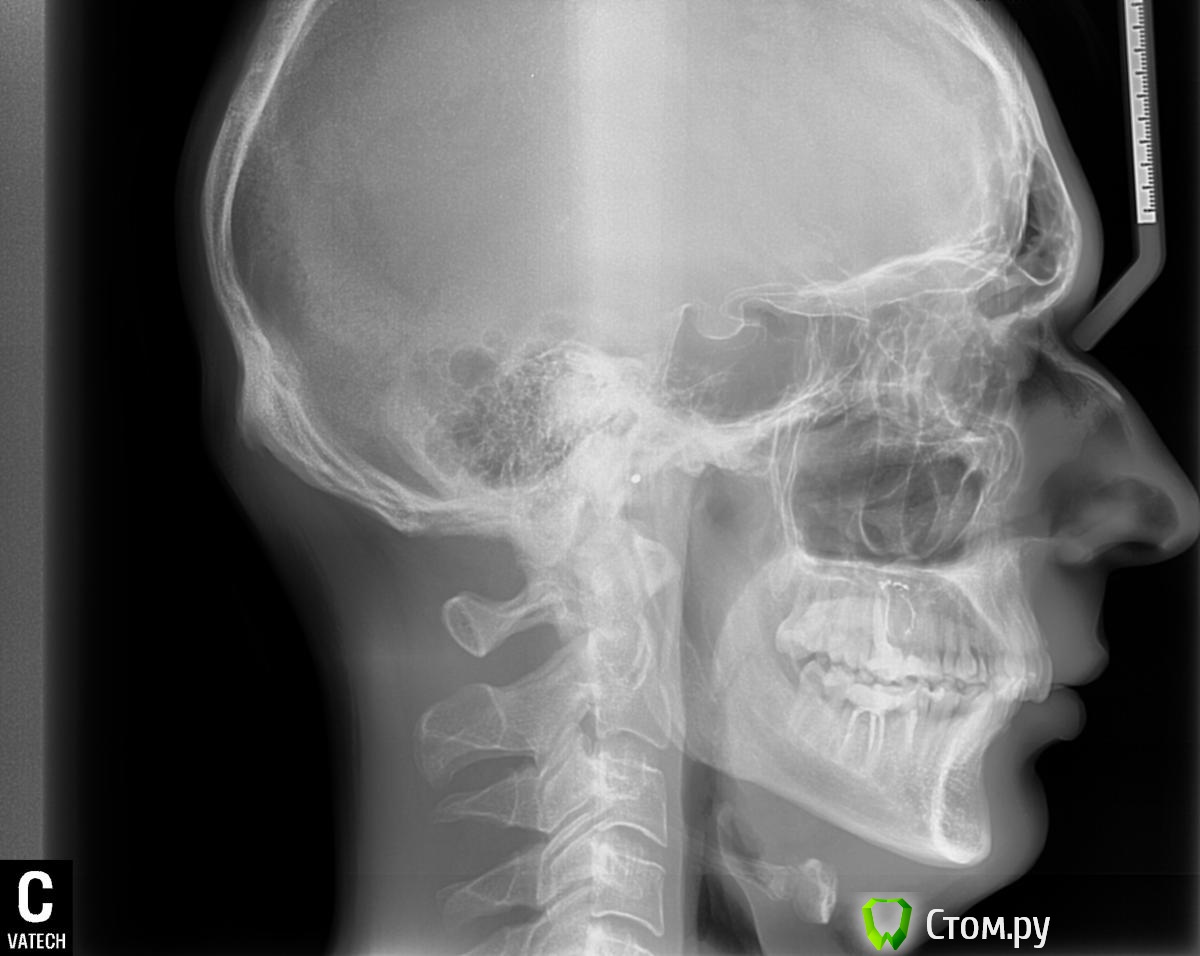

2.          Цефалометрия

1. =81(незначит протрузия или норма?)

2. =79

3. =3

Ось =69(уже горизонтальный или еще норма?)

1. -mp=22(явный горизонтальный тип роста)

2. =3.5 мм( 2 скелетный класс)

Межрезцовый(плохо видно на ТРГ,я посчитал )=129

Угол резцов вч=106

Угол резцов нч=103(возможно тут я ошибся)

По данным углов,согласно фастлайта, углы уже в пределах компенсации

Напрашиваеться вывод,если поработают брекеты,то угол резцов вч увеличиться,нч уменьшиться,и между резцами будет отсутствовать контакт